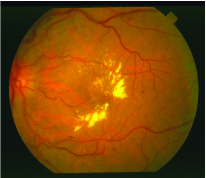

Retinal blood vessels The STructured Analysis of the Retina (STARE) dataset was used in this case study. The dataset consists of twenty colour retinal images, which for the purposes of this study are treated as a single image ( and ). An example image is presented in Figure 1d. A mask was formed which delineates the pixels that fall outside the retina by thesholding the intensity of the red channel at a value of (the black area) and these pixels were excluded from the experiments. The dataset contains two annotations which delineate the blood vessels in the image.